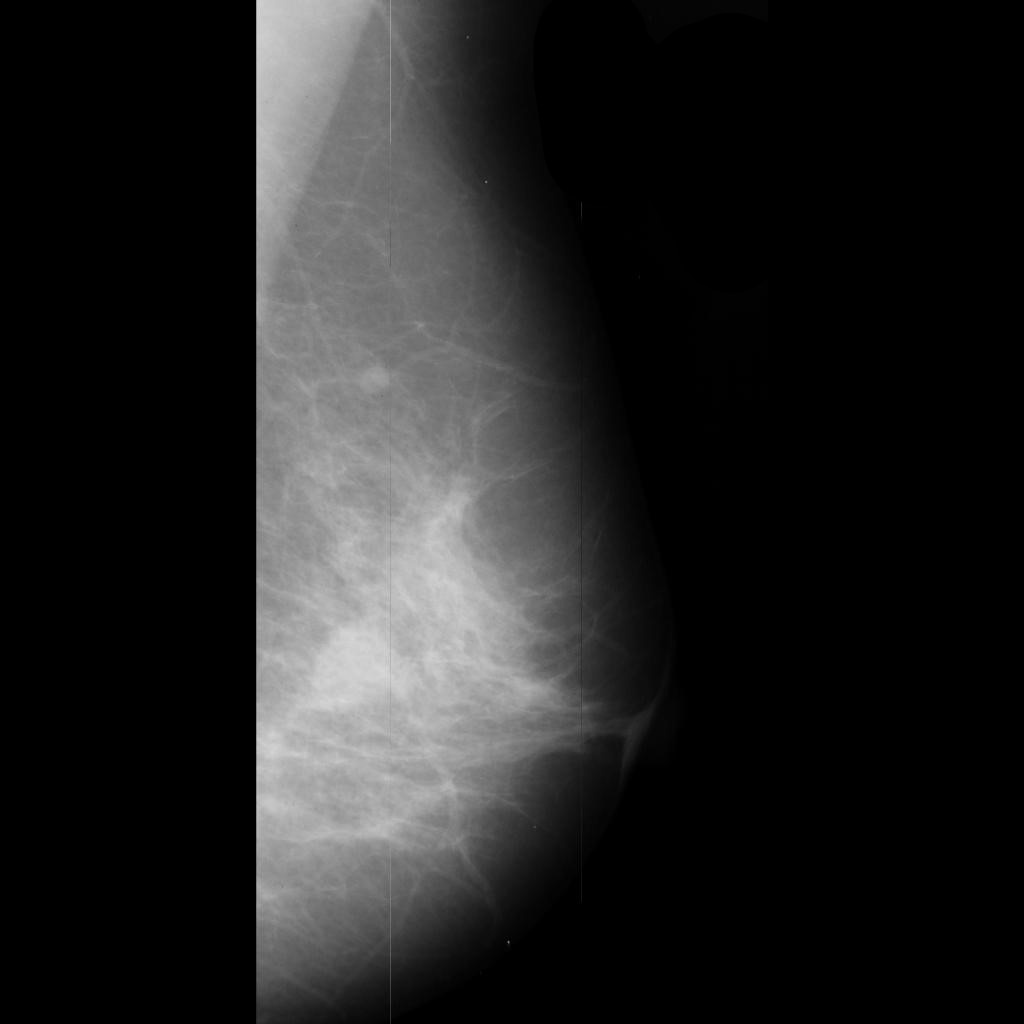

benign